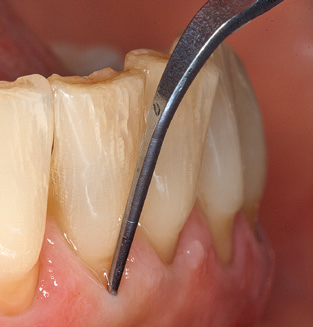

Das aktuelle Arbeitskonzept für die UPT

Abb. 4: Für das Sondieren an dentalen Implantaten sind biegsame, millimeterskalierte Sonden empfehlenswert (z.B. Colorvue Kit PCV11KIT6, Hu-Friedy). – Abb. 5a und b: Eine gerade Arbeitsspitze (1P, W&H Dentalwerk Bürmoos GmbH) ist universell für die Instrumentierung natürlicher Zähne geeignet. – Abb. 6: Für die Bearbeitung schwer zugänglicher Bereiche der Zahn- und Wurzeloberflächen (z.B. Furkationen) bieten sich gebogene Arbeitsspitzen (3Pr/3Pl, W&H Dentalwerk Bürmoos GmbH) an. – Abb. 7: Die spitz zulaufende sechseckige Implantatreinigungsspitze (1I, W&H Dentalwerk Bürmoos GmbH) ermöglicht eine atraumatische und effiziente Reinigung der Kronen- und Abutmentoberflächen. – Abb. 8: Für die manuelle Instrumentierung der Implantatoberflächen sind Titan- oder Carbonküretten geeignet.

Die gute Ausleuchtung des Arbeitsfeldes stellt eine wesentliche Erleichterung dar. Bei dem von den Autoren genutzten System ist dies gelungen, indem ein 5­facher LED­Ring in das Handstück integriert wurde. Natürlich werden für dieses System unterschiedliche Arbeitsspitzen für die jeweiligen Indikationsbereiche angeboten. Eine gerade, universell einsetzbare Spitze ist das Basisinstrument zur maschinellen Instrumentierung natürlicher Zähne (Abb. 5a und b). Für schwer zugängliche Bereiche im Seitenzahnbereich werden gebogene Spitzen angeboten, die auch einen Zugang zu freiliegenden Furkationen ermöglichen (Abb. 6).